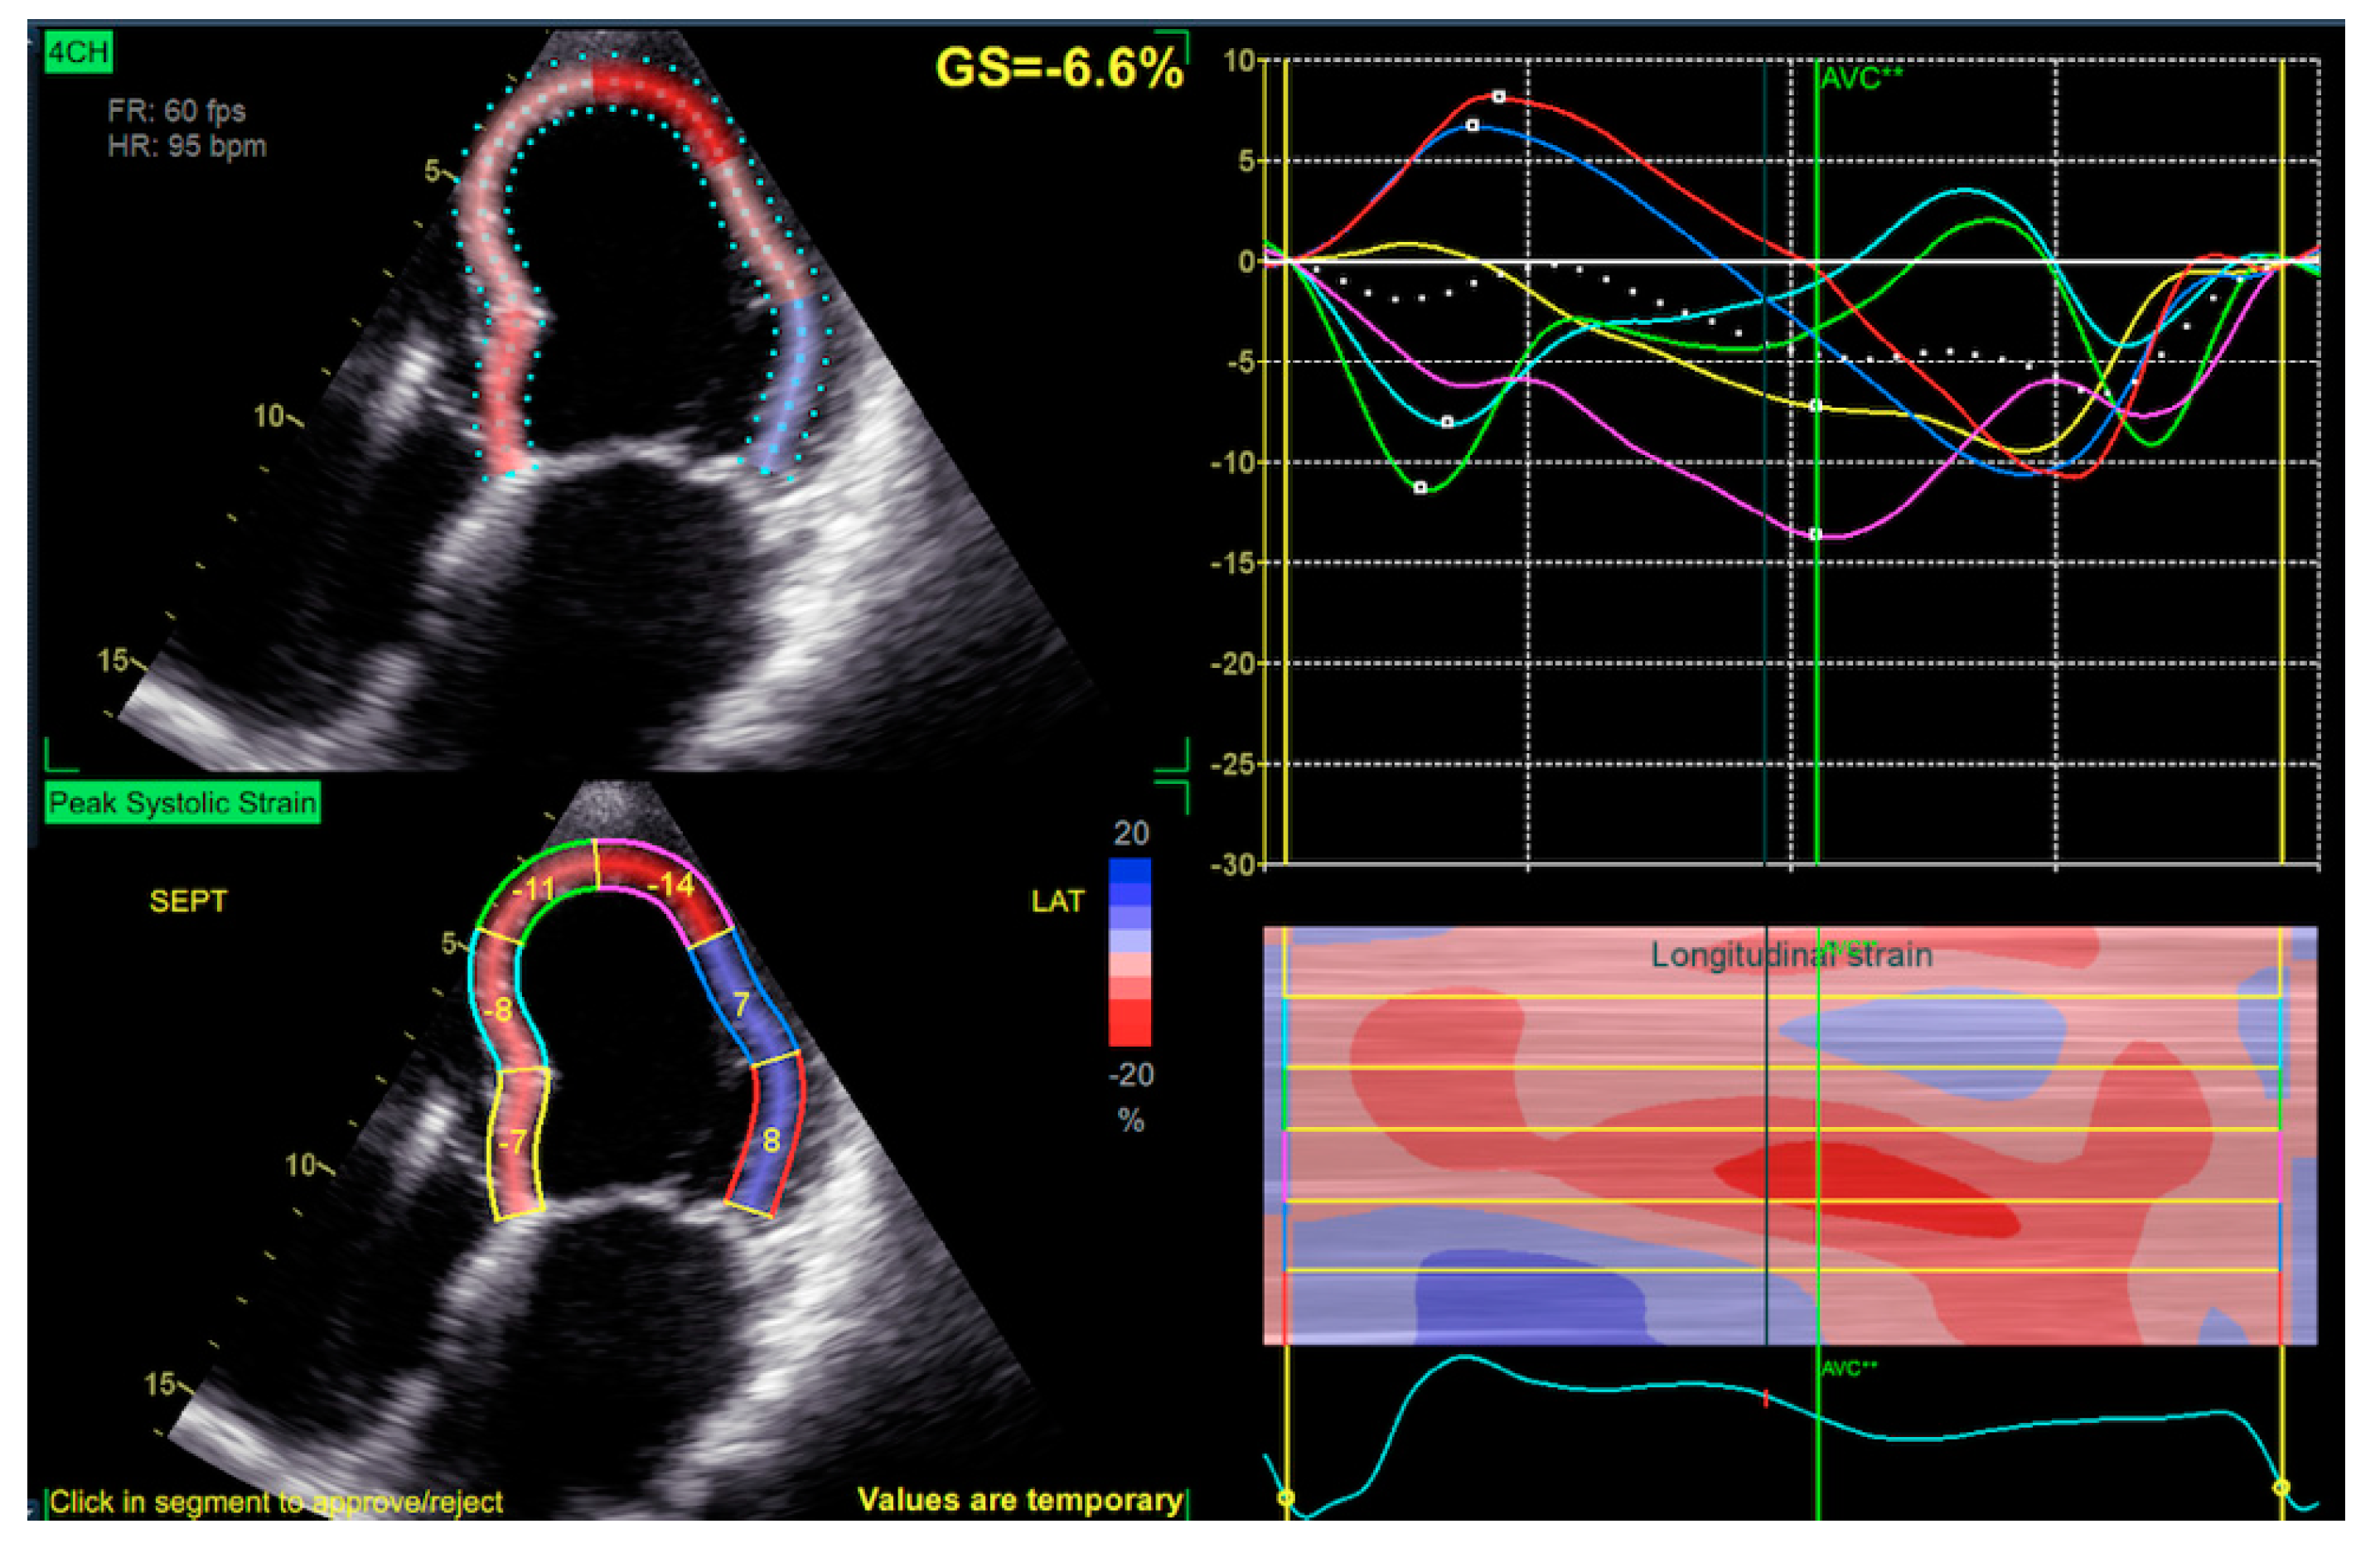

The Agreement of a Two- and a Three-Dimensional Speckle-Tracking Global Longitudinal Strain

2. Materials and Methods

2.2. Echocardiography